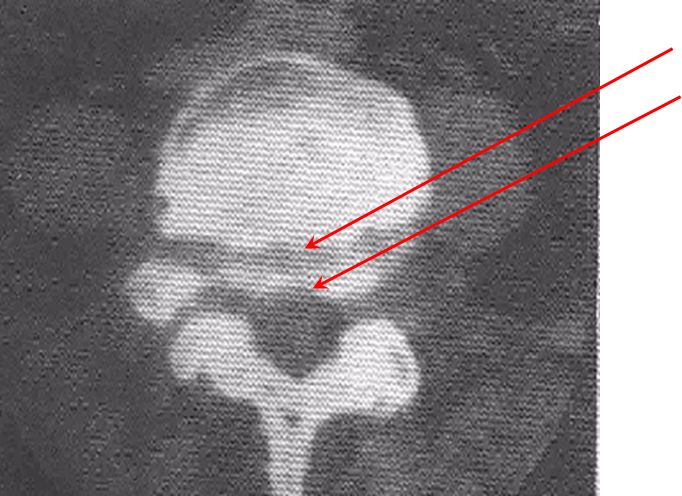

图示:椎弓崩裂伴脊柱滑脱(侧位),第四腰椎椎弓崩裂,伴第四腰椎椎体向前滑脱,箭头示棘突后缘曲线异常。

斜位片:可清晰显示峡部病变。在椎弓崩裂时,峡部可出现一带状裂隙,称为苏格兰(Scotty)狗颈断裂征或长颈犬(Greyhound)征。其前下方常位于骶骨上关节突顶点上数毫米,偶尔可位于顶点的稍前方。